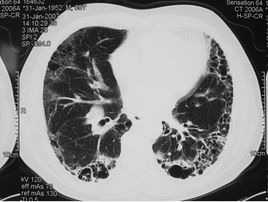

2.X線檢查

早期雖有呼吸困難,但X線胸片可能基本正常;中後期出現兩肺中下野彌散性網狀或結節狀陰影,偶見胸膜腔積液,增厚或鈣化。